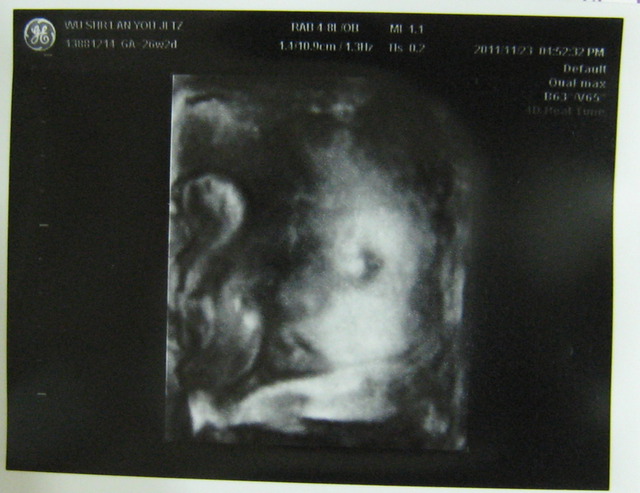

有,次也做4D,然我看到的是模糊的影像,但有次看到瓦力正在打哈欠?的子,我得好好玩,也很多人有看胎在肚子打哈欠(嘴巴)的子,所以跟大家分享。往下看就找到喔。